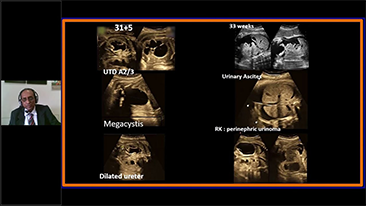

AlimentÊe par la plateforme avancÊe ZST+, la gamme complète de solutions intelligentes Nuewa est con?ue spÊcialement pour amÊliorer la santÊ des femmes avant, pendant et après la grossesse, de manière à poser des diagnostics complets et efficaces pour rÊpondre à des dÊfis cliniques de plus en plus exigeants.